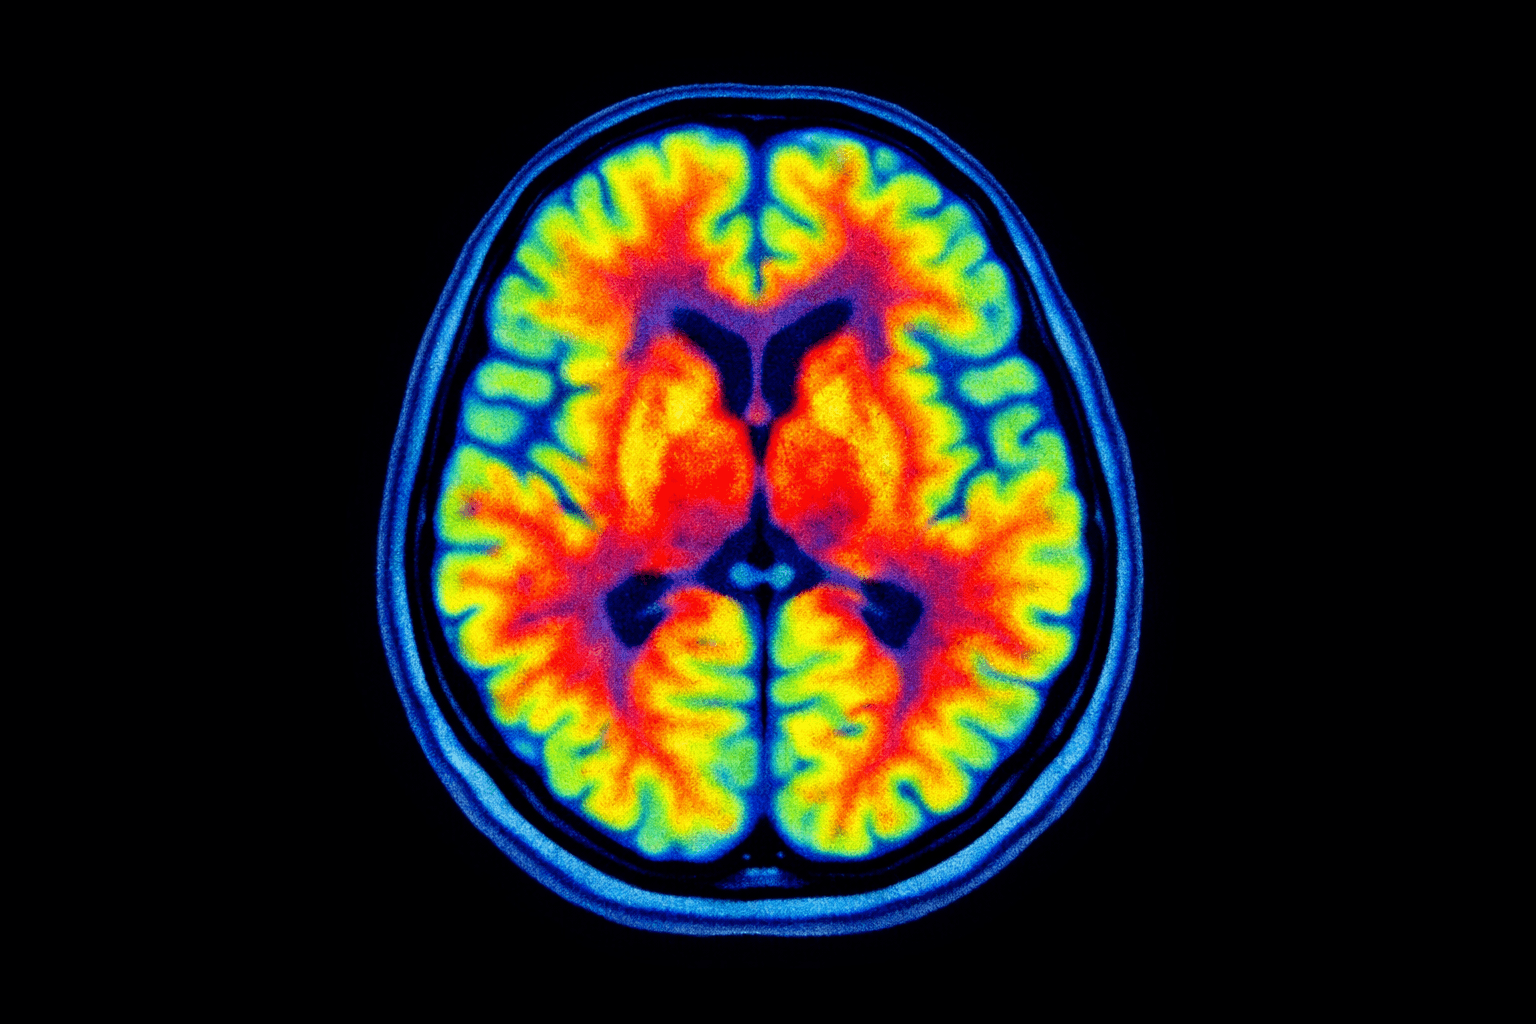

El radiofármaco es una de las herramientas más útiles y controladas de la medicina actual. Aquí te explico qué es, cómo se usa y por qué su papel es tan importante en los estudios nucleares.

Muchas veces, la palabra “radiofármaco” suena intimidante, pero en realidad es parte de una herramienta muy precisa que usamos todos los días para ver lo que otras técnicas no muestran. Me parece importante explicarlo con claridad, sin tecnicismos ni exageraciones, para que quienes van a recibir uno lo entiendan sin miedo y con confianza.